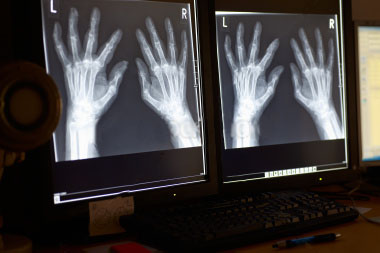

More on Osteoporosis

Danny Miranda2021-09-22T13:48:11+00:00More on Osteoporosis More on Osteoporosis There are a number of reasons why I chose the topic of osteoporosis for my article this month. I have written many articles on osteoporosis over the past 29 years in which tremendous changes have occurred in both the diagnosis and treatment of the disease. Today I [...]